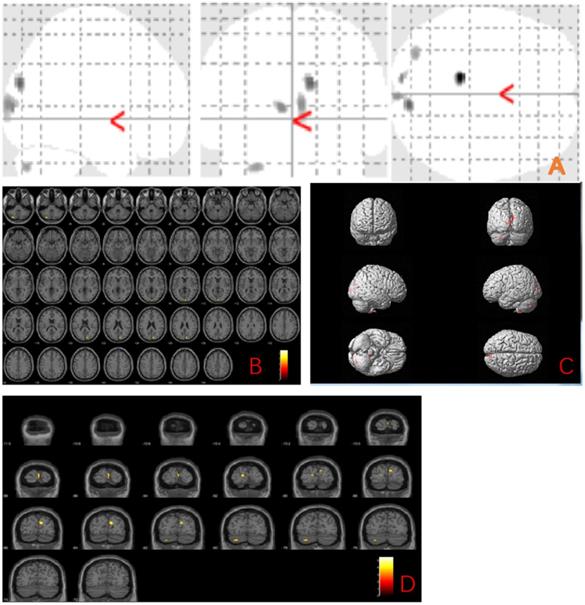

The MBI group showed gray matter atrophy in the left brainstem, right temporal transverse gyrus, left superior temporal gyrus, left inferior temporal gyrus, left middle temporal gyrus, right occipital pole, right thalamus, left precentral gyrus and left middle frontal gyrus (uncorrected p < 0.001) compared to the normal control group (Fig. 1 and Table 2).

Figure 1

Anatomic location of brain regions showing significant gray matter volume decrease in the mild behavioral impairment group compared to the control group. Upper panel: Maximum density transparency graphs (A), where gray matter volume reduction was labeled with grey color. Lower panel: Horizontal (B), coronal (D) brain graphs, where gray matter volume reduction was labeled with yellow color; 3-D brain surface rendering graphs (C), where gray matter volume reduction was labeled with red color.

Table 2

Voxel-based morphometry differences between mild behavioral impairment group (n=16) and control group (n=18)

Cluster size (voxel)Peak levelMNI Coordinates (mm)T valueP uncorrected

xyz

68left brainstem-11-38-604.560.000

130right temporal transverse gyrus42-2464.540.000

65Right Thalamus17-14-24.230.000

40left superior temporal gyrus-450-214.190.000

54left inferior temporal gyrus-45-41-214.160.000

89right occipital pole3-9584.140.000

23left precentral gyrus-658123.970.000

56left middle temporal gyrus-53-6253.810.000

29left middle frontal gyrus-3235203.770.000